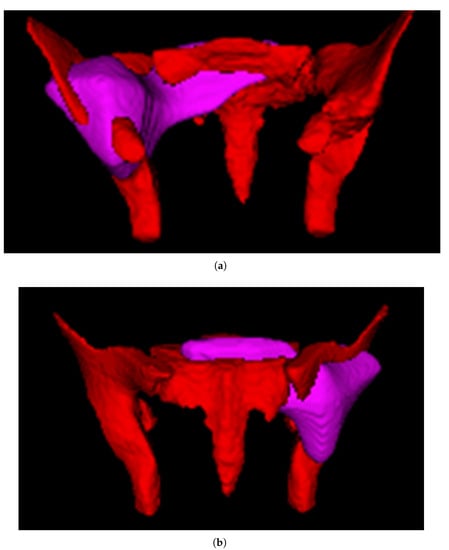

After training, we merged the 4-fold models used above by averaging the prediction scores, and tested the merged model on the separate test set, consisting of images of 25 patients unused in the training process; the results of each fold on the test set are presented in Table 5. The accuracy of the model in terms of the test set was 0.800, the precision of the model was 0.786, and the specificity, recall, and F1 score were 0.750, 0.846, and 0.815, respectively. The Receiver Operating Characteristic (ROC) curve and Precision-Recall (P-R) curve are shown in Figure 7, the Area Under Curve (AUC) was 0.78 and the Average Precision (AP) was 0.69. The confusion matrix results of the merged model in the training set and test set are shown in Figure 8. Then, all the 4-fold established models were taken for the subsequent experiments to generate the visible heatmaps of the region’s attention. In Figure 9, after the non-rigid registration process, we took the mean results of the heatmap generated from layer 4 in the network, and voxels with the top 64,000 (around 0.5%) heat scores were highlighted. As shown in Figure 9, the purple region indicates the concentration of factors causing difficulty.

Figure 9.

Highlighted heatmap of the attention region. (a) anterior view. (b) posterior view.

Up to now, the current preoperative assessment method for this task is mainly based on manual measurement. However, manual measurement has the problems of anatomical marker selection and poor consistency among the patients. The AI system is able to extract the distance information more effectively to obtain better results. This study made the first attempt to establish a difficulty-prediction model by using AI. Although the AI system cannot fully replace the manual measurements for now, it is able to provide at least an additional preliminary judgment for the surgery. The model has shown good accuracy and reliability, which has the potential to assist surgeons in judging the surgical difficulty preoperatively and in choosing the optimal surgical approach for patients with rectal cancer (Figure 5). MRI images and clinical characters subjected to this model would output a prediction result (difficult or non-difficult). For patients categorized as difficult, transanal approaches are supposed to be considered, since the transabdominal approach may not have the ability to mobilize and resect the rectum in the deep narrow pelvis of patients. In contrast, for patients analyzed as non-difficult, surgeons could perform transabdominal surgery with confidence. Remaining as one of the top fields of AI, the calculation process of the AI model cannot be fully demonstrated by traditional parameters. Fortunately, the output heatmap drawn by CAM could show the attention region of the model, which could be aligned, to some extent, in clinical practice. As shown in Figure 9, the purple highlighted region was the key attention region affecting (pelvic) difficulty, nd was used by the AI model to judge the difficulty of surgery. The shape of this area was irregular and extended to the ilia and sacrococcyx, indicating that these structures had adverse influences on difficulty. The ilium confined the approach of surgical instruments and limited the bilateral dissection of the rectum in the deep and narrow pelvic cavity, which was consistent with the intraoperative experience of the surgeon. In the meanwhile, the rectum lies close to the posterior surface of the prostate, which adds the difficulty of dissection in males. In conclusion, the algorithm we created in this study could automatically extract characteristics and consequently develop a reliable prediction model. Besides this, the results of the heat map results also showed that the network exhibits a focus on the position relationship between the hip and ilium, and further study could help us to better simplify and optimize the manual measurement method, which we are considering for further research in the future.